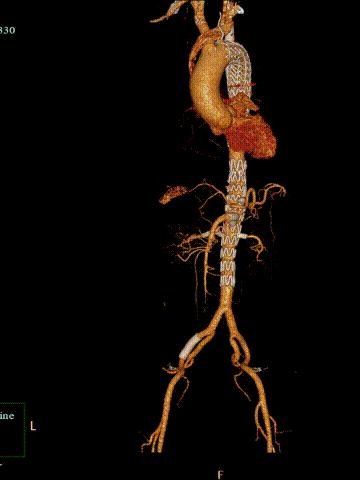

造影提示胸腹主动脉夹层封堵满意,假腔无显影,无内漏。分支动脉及髂动脉血流通畅。

最后造影

术后随访结果

术后1个月及3个月的CTA均提示胸腹主动脉重塑良好,无内漏,分支支架无狭窄闭塞。

术后1月CTA

术后3月CTA